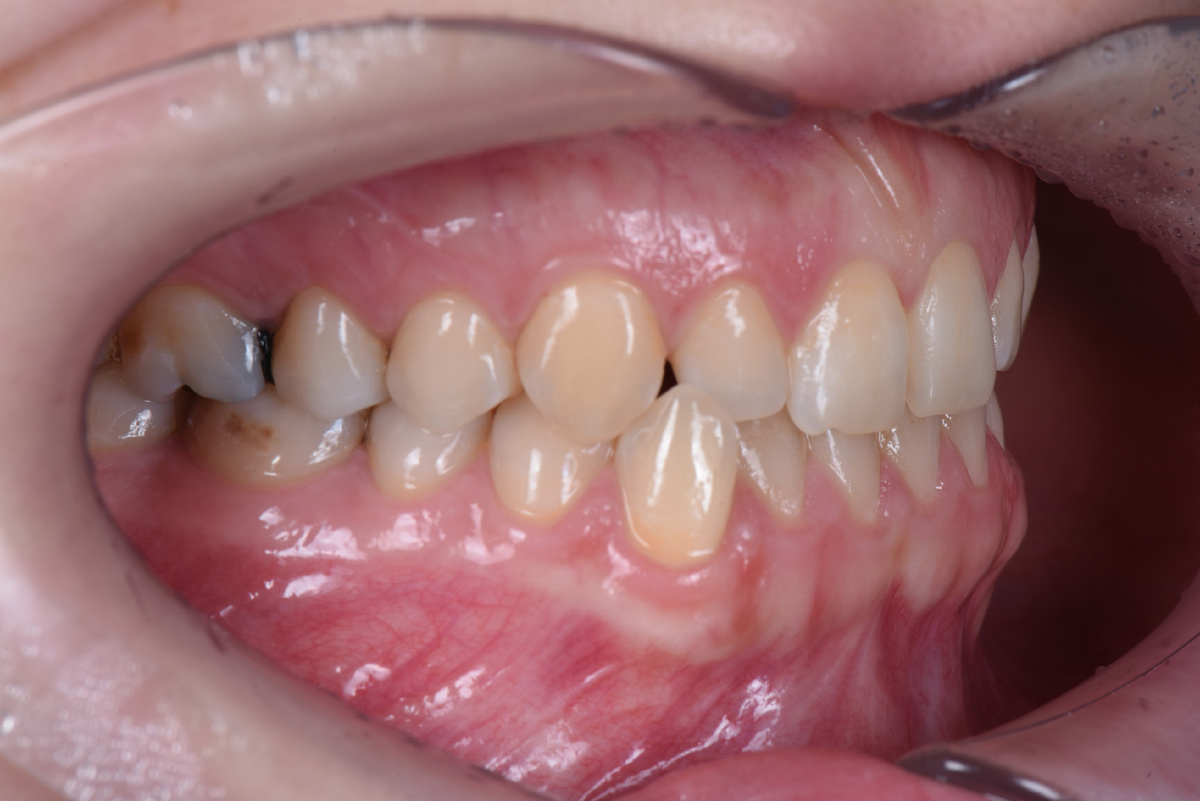

Хотя прикус Марии можно было условно отнести к первому классу, тенденция к третьему классу уже начала проявляться. Верхние и нижние передние зубы начали стираться, а нижний клык из-за неправильного положения создавал дополнительную нагрузку на челюсть.

Клык (4.3) в обратном перекрытии